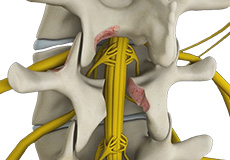

Lumbar Laminectomy

Lumbar laminectomy is a spinal surgery to relieve excess pressure on the spinal cord or nerves within the spinal canal in the lumbar or lower back region. The pressure may be caused by bony overgrowths, herniated discs, injury, tumors, or narrowing of the spinal canal resulting in painful symptoms affecting a person’s ability to perform normal day to day activities.